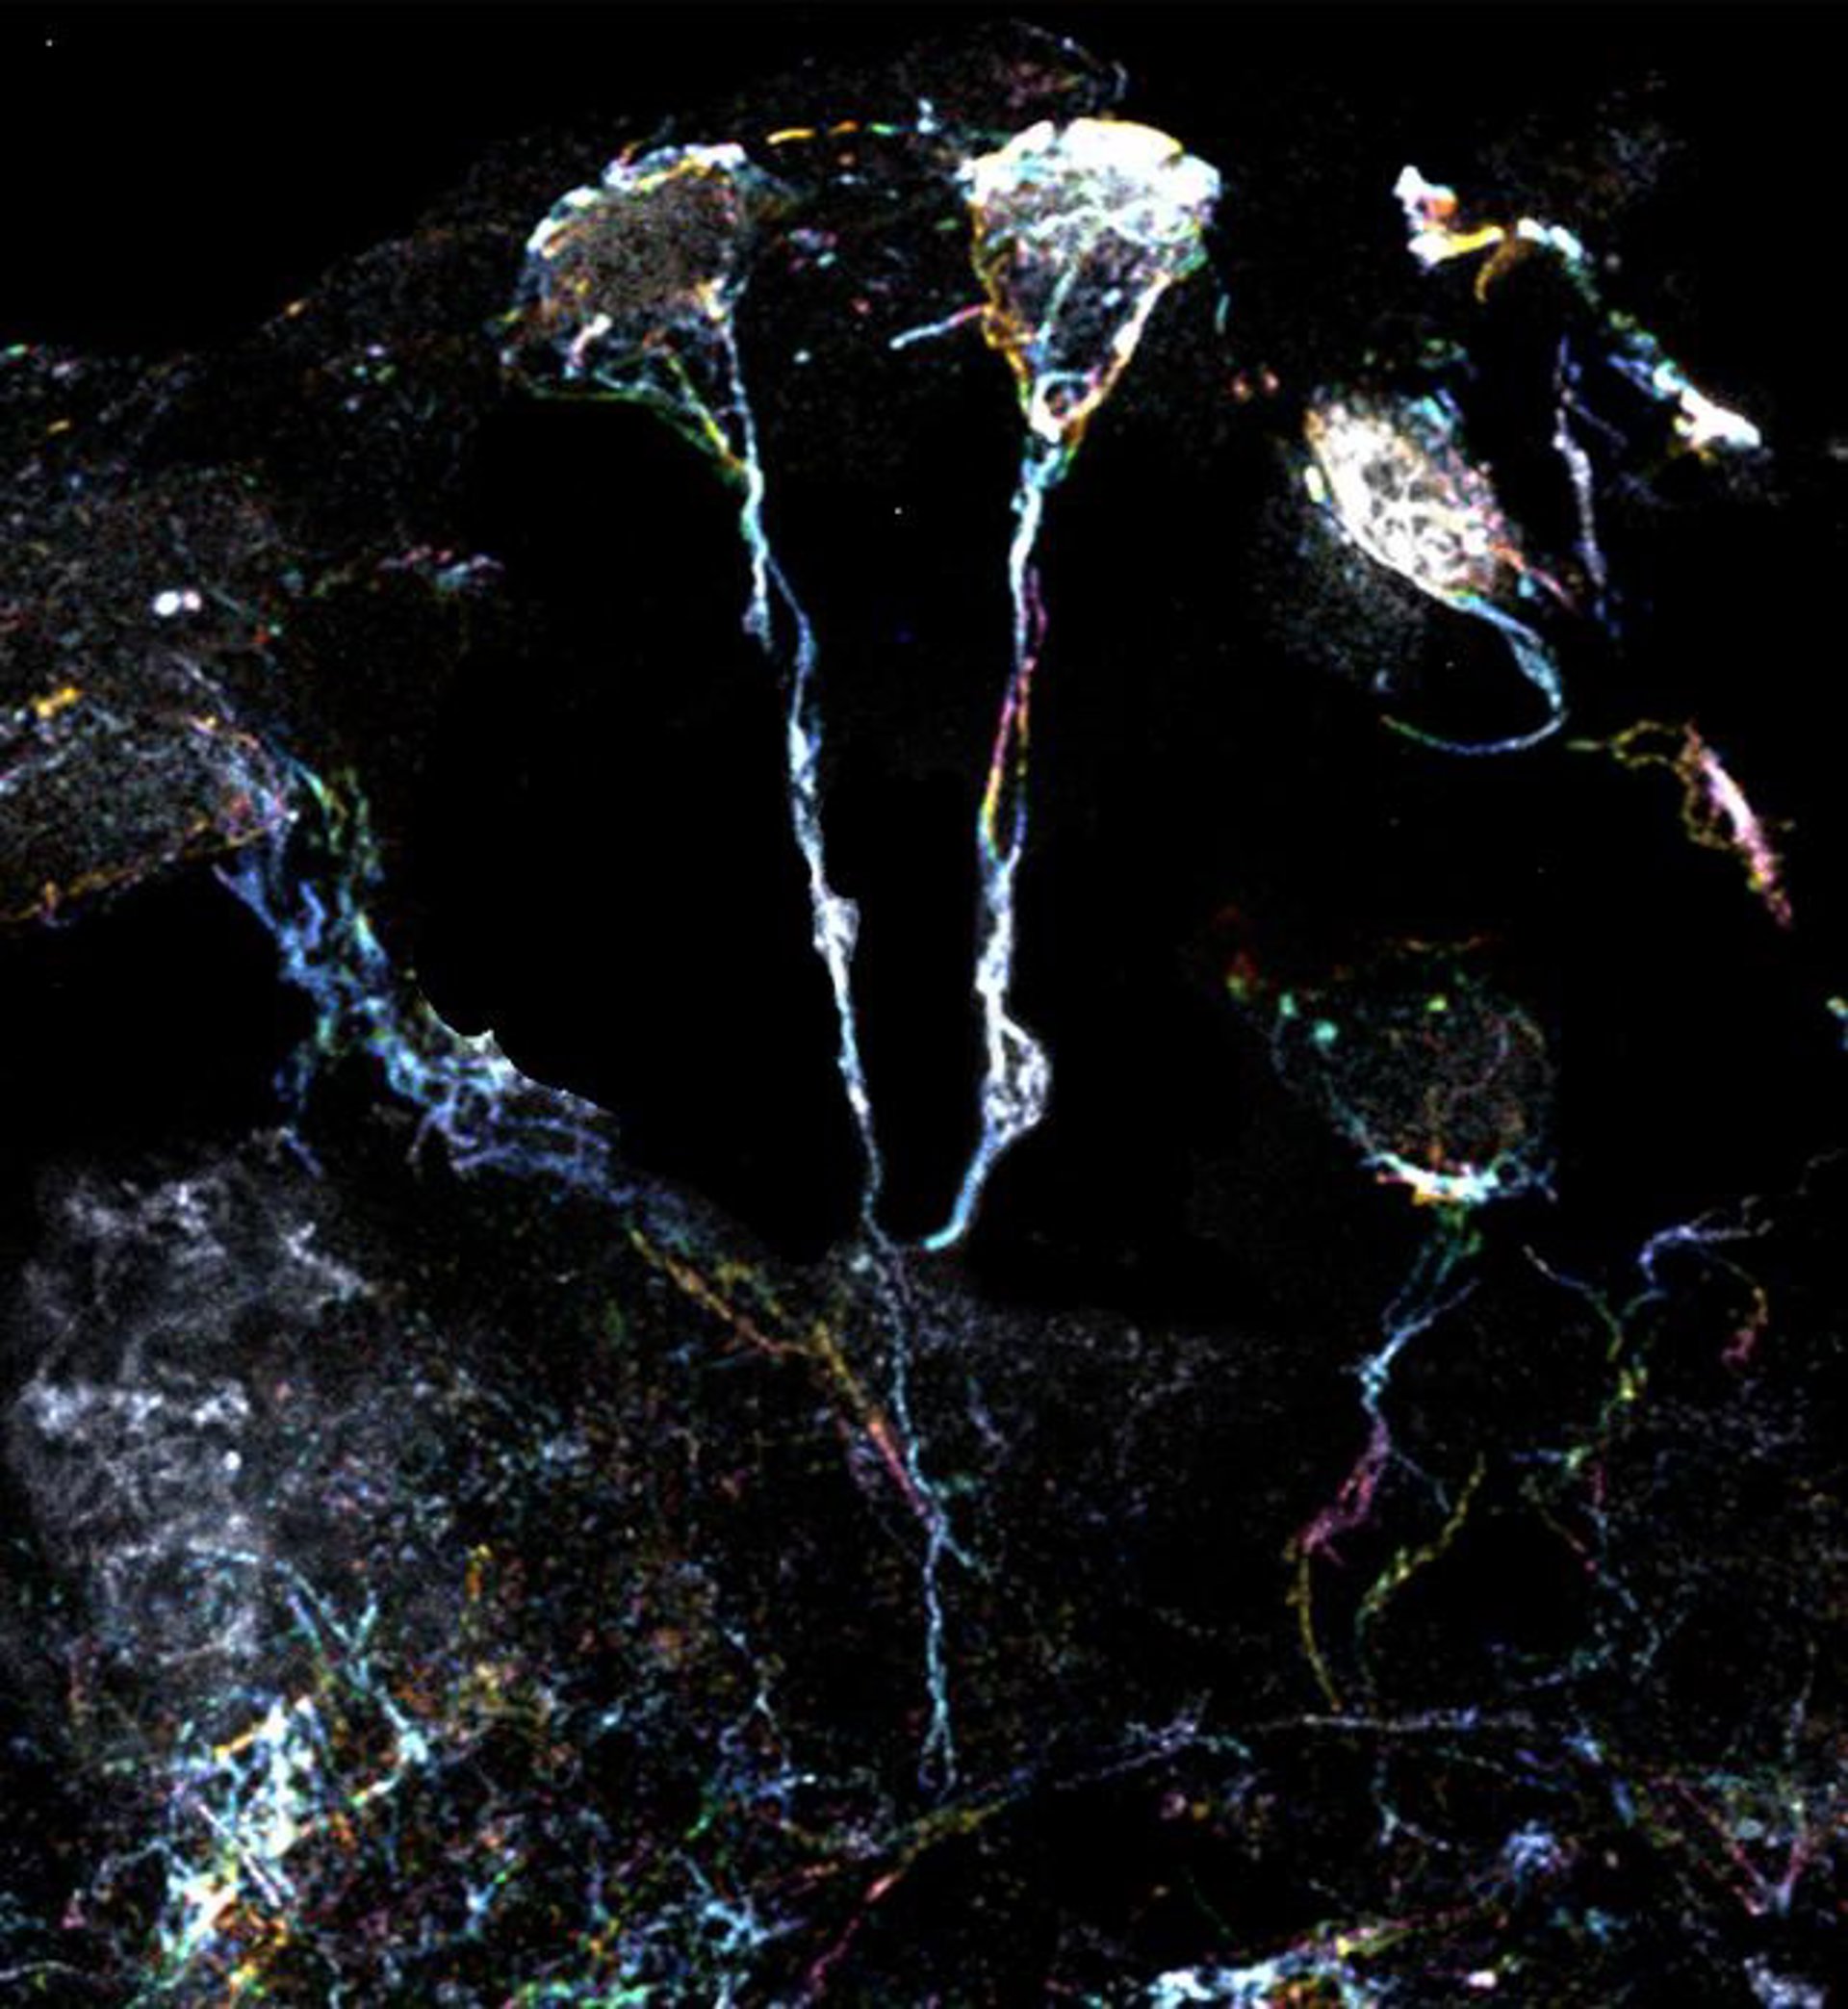

Imagen de células madre neurales  de la mosca de la fruta.

Imagen de células madre neurales de la mosca de la fruta. - DUKE-NUS MEDICAL SCHOOL

Mediante microscopía de superresolución con una potencia de aumento 10 veces superior, el equipo de científicos examinó las diminutas estructuras de fibra que caracterizan a las células madre neurales latentes de las moscas de la fruta.

Estas finas estructuras, 20 veces más pequeñas que el diámetro de un cabello humano, son protuberancias que se extienden desde el cuerpo celular, y son ricas en actina o filamentos proteicos. Un tipo específico de proteína formina puede activar estos filamentos y provocar su ensamblaje.